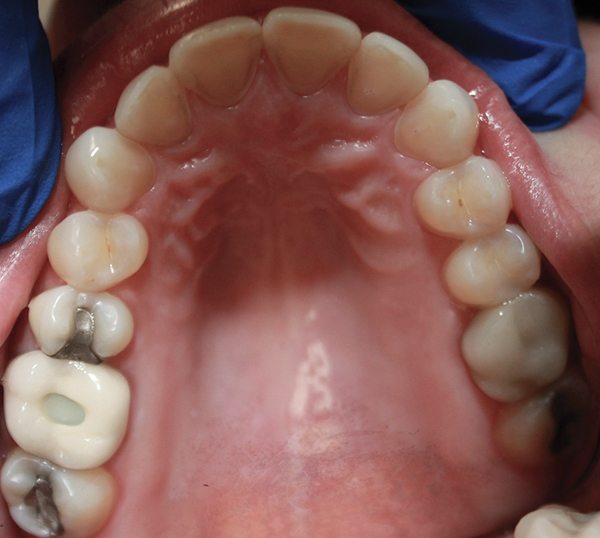

After several years and many consultations, the patient finally agreed to move forward with the recommended treatment. The patient's pretreatment condition is depicted in Figure 1 through Figure 3. Upon evaluation, several conditions were documented. The observation of a more coronally positioned gingival margin on the maxillary anterior teeth was noted. The differential diagnosis of dentoalvealor extrusion versus altered passive eruption was considered. The process of altered passive eruption was ruled out after appropriate bone sounding and palpation of the cemento-enamel junction (CEJ) apical to tooth Nos. 7 through 10. The gingival margin and bone heights were determined to be localized in a normal position within the gingival sulcus. This confirmed the diagnosis of dentoalveloar extrusion.10 As the linguals of the upper teeth were destroyed with acidic exposure, the teeth continued to erupt into function. Observations also included buccal collapse of the arches, malalignment of teeth, incisal wear, and dentoalveolar extrusion of the lower anterior teeth. A thorough smile design work-up was completed using numerous intraoral and extraoral radiographs and photographs. The lower incisal edges, particularly of tooth Nos. 24 and 25 showed signs of extrusion and wear but since the incisal edges closely followed the curvature of the lower lip line and the patient was only interested in maxillary treatment, their intrusion was limited to leveling and aligning the incisal edges. The preferred treatment option in this type of case is to consider orthodontic intrusion of maxillary teeth to relevel the gingival margins and subsequently increase occlusal clearance between arches for restorations. At that point, a treatment plan was developed that would address incisal edge position, which had shortened over time, and the appearance of gingiva versus tooth structure during a full smile.11 In addition, the photographs were used to evaluate the curvature of her smile, the midline of the teeth to the face, and the overall esthetics of the smile.

Fig 4. Initial orthodontic situation, showing patient’s relaxed smile with worn incisal edge display..

Figure 4